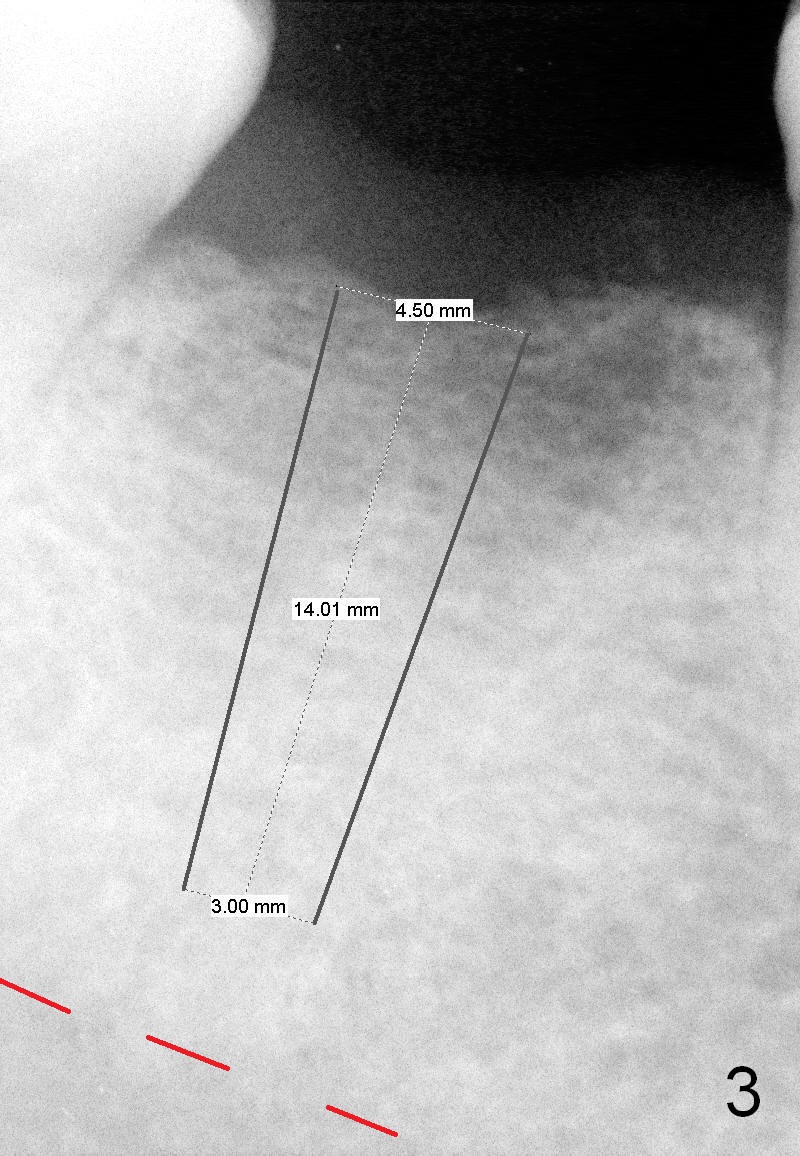

A 52-year-old lady has lost #30 for several years, but the socket outline persists with low bone density (Fig.1 (trimmed from panoramus),2). Osteotomy should be underprep. Bone height allows to placement of a 14 mm implant (Fig.3). Still initial depth will be 12 mm.